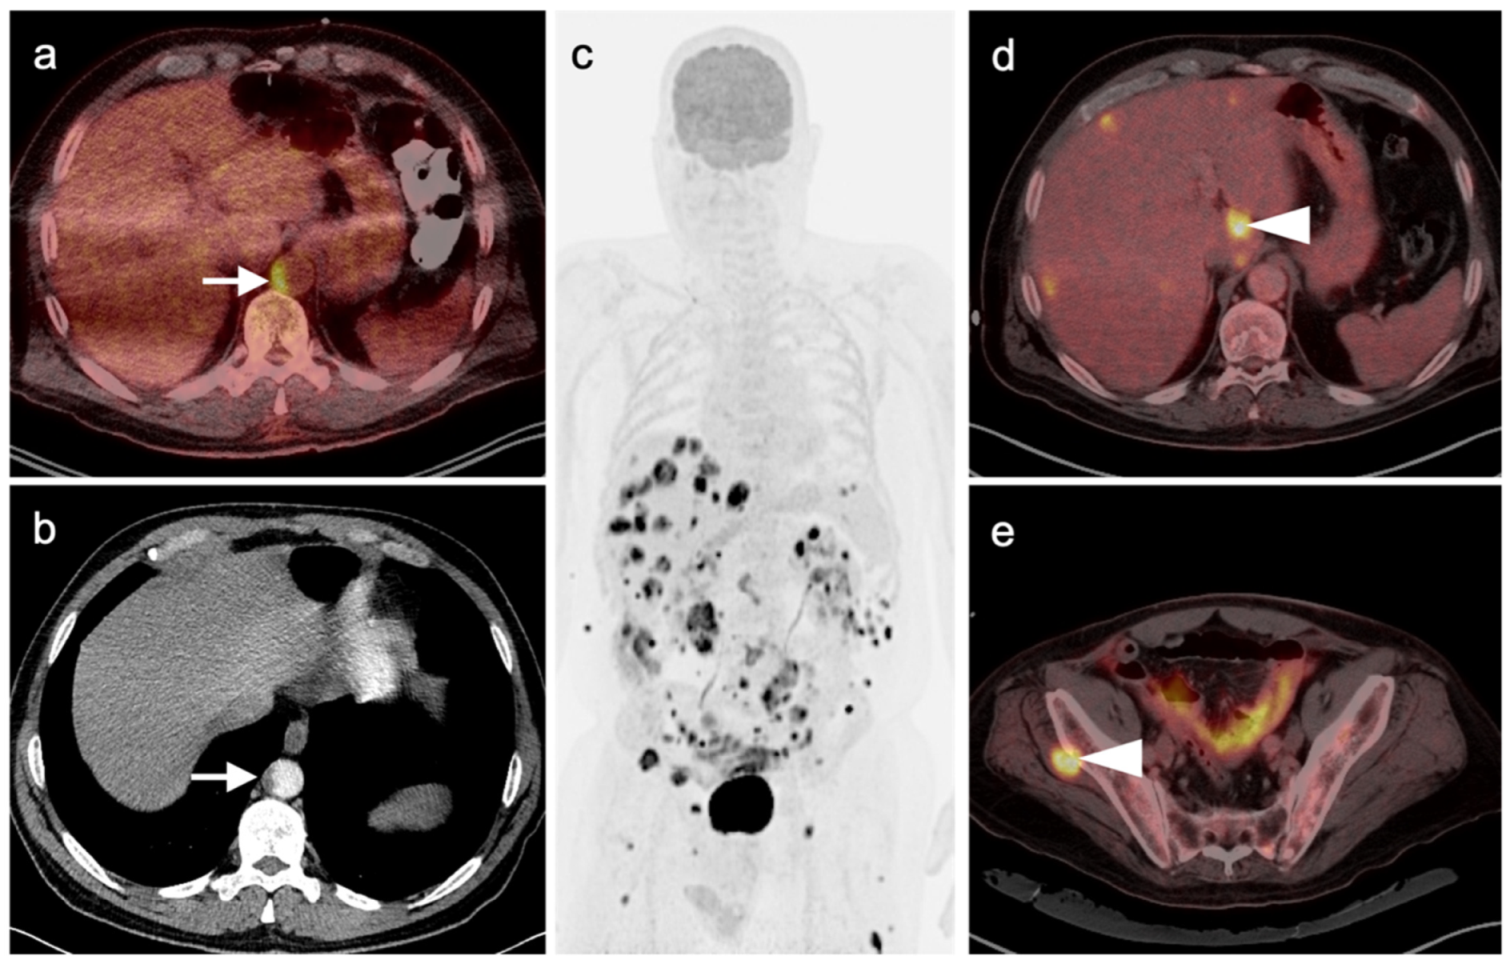

3.1.5. Rhabdomyosarcoma